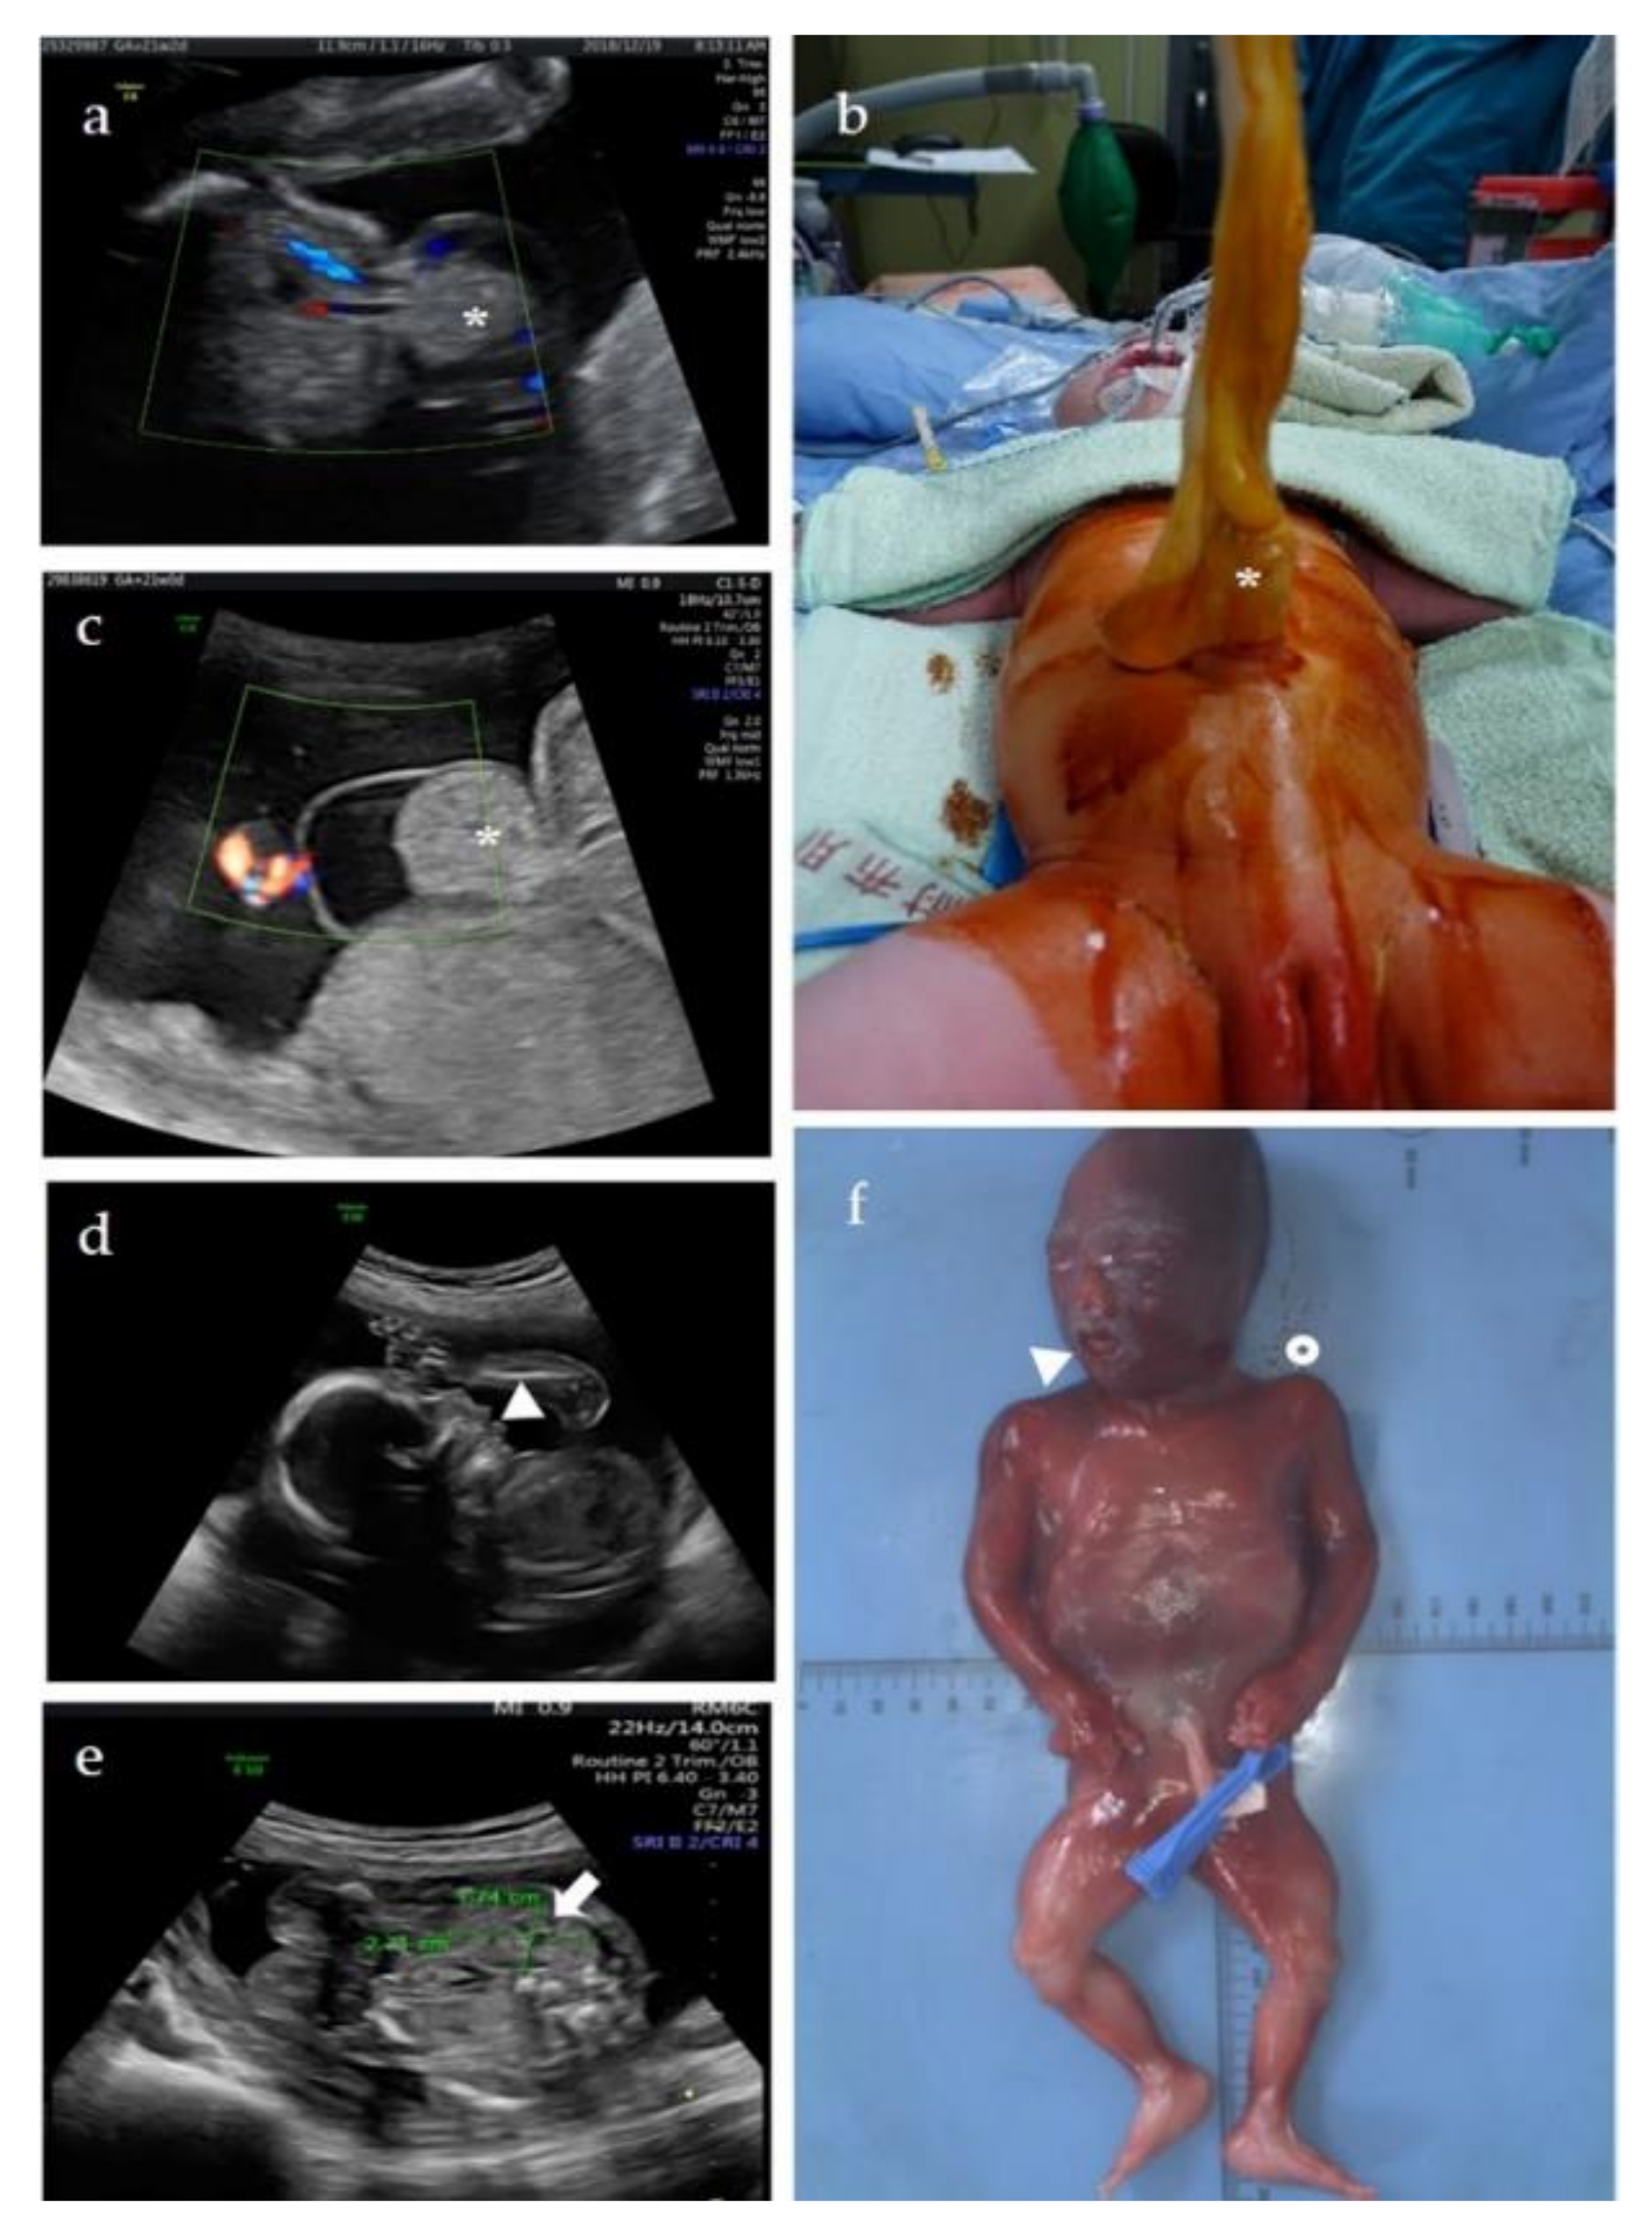

Figure 3.

Clinical features of three patients with BWS. Patient 1 (a,b): Prenatal ultrasonography identified (a) isolated umbilical hernia (star) at GA = 21 weeks and two days. The position of cord insertion was normal and protruding small intestine was noted. (b) The umbilical hernia with 3 cm abdominal wall defect and small bowel protruding (star) was identified after birth (GA = 38 weeks). Macrosomia with body weight of 3850 g (96th percentile) was also noted. Patient 2 (c): Prenatal ultrasonography identified (c) isolated omphalocele (star) at GA = 21 weeks. The cord inserted on the apex of herniated sac. Patient 3 (d–f): Prenatal ultrasonography identified (d) protruding tongue (triangle) and (e) unilateral nephromegaly (fetal kidney length: 2.71 cm and transverse diameter: 1.74 cm; both values > 95th percentile) (arrow) at GA = 20 weeks and two days. (f) Macroglossia (triangle), board nose, and hemihyperplasia (circle) were further identified after TOP at GA = 21 weeks and 3 days.

A 31-year-old Taiwanese woman who naturally conceived, gravida 1, para 0, received prenatal care at our center since the first trimester. Isolated umbilical hernia (Figure 3a) was found at GA = 21 weeks and two days, but otherwise, no other structural abnormality was noted. The estimated fetal weight was 460 g (79th percentile). BWS was not speculated due to our inexperience of fetal BWS diagnosis then. Cytogenetic analyses and chromosome microarray analysis (CMA) were offered to detect if any chromosomal/genomic variants associated with the fetal anomaly. Results of both tests showed a normal female karyotype without pathogenic copy number variations (CNVs), 46,XX.arr(X,1−22)×2. The parents decided to continue the pregnancy, and the pregnancy was uneventful until birth. A female baby was delivered at GA = 38 weeks by cesarean section. The birth body weight was 3850 g (96th percentile), and Apgar score after birth were 8 and 9 in the first minute and fifth minutes, respectively. Macrosomia, in addition to umbilical hernia with 3 cm abdominal wall defect and small bowel protruding (Figure 3b), was noted, leading to suggest of BWS. However, neither neonatal hypoglycemia nor asymmetric extremities was found. Neonatal abdominal ultrasonography revealed normal size of kidney and liver without intraabdominal tumor. Surgery of umbilical hernia repair with small bowel reduction was arranged at the first day after birth, and the baby was discharged without complication a few days later. Methylation-specific multiplex ligation-dependent probe amplification (MS-MLPA) test of neonatal peripheral blood for BWS was performed, and the result showed ICR2 hypomethylation (8.3%) on chromosome 11p15, confirming the diagnosis of BWS. The methylation status in ICR1 was within the normal range (48.9%). No copy number change was detected in ICR1 and ICR2.

During this pregnancy, chorionic villus sampling (CVS) was provided at GA = 12 weeks. The crown-rump length of the fetus was 63.2 mm (estimated GA = 12 weeks and 5 days). Chromosomal analysis revealed a normal female 46,XX karyotype. CMA identified a 32 kb deletion on chromosome 11p15.5, (arr[GRCh37] 11p15.5(1996741_2028877)×1), identical to that found in the first pregnancy (Figure 1). Parental follow-up showed the 11p15.5 deletion is of maternal origin. The mother carried the 11p15.5 deletion in mosaicism (arr[GRCh37] 11p15.5(1996741_2028877)×1~2) without phenotypical abnormality. MS-MLPA of the villi, maternal blood, and paternal blood revealed 1, 1.53, and 2 copies in the H19 gene, respectively. The methylation status of the ICR1 in the villi, maternal blood, and paternal blood are hypermethylation (98.2%), hypomethylation (37.5%), and normal methylation (50%), respectively. The copy number and methylation status of villi and bloods of both parents in ICR2 were normal. The fetus was diagnosed with BWS. Detailed ultrasonography performed at GA = 20 weeks and two days showed protruding tongue (macroglossia) (Figure 3d) and nephromegaly, in which both fetal kidney length (2.71 cm) and transverse diameter (1.74 cm) were above 95th percentile (Figure 3e) [20]. The couple decided to terminate the pregnancy. TOP was performed at GA = 21 weeks and 3 days, and a 585 g (> 97th percentile) female fetus was aborted. Postmortem examination showed macroglossia, a broad nose, clear anterior ear creases, visceromegaly (including lung, kidney, and adrenal gland), and hemihyperplasia (Figure 3f).